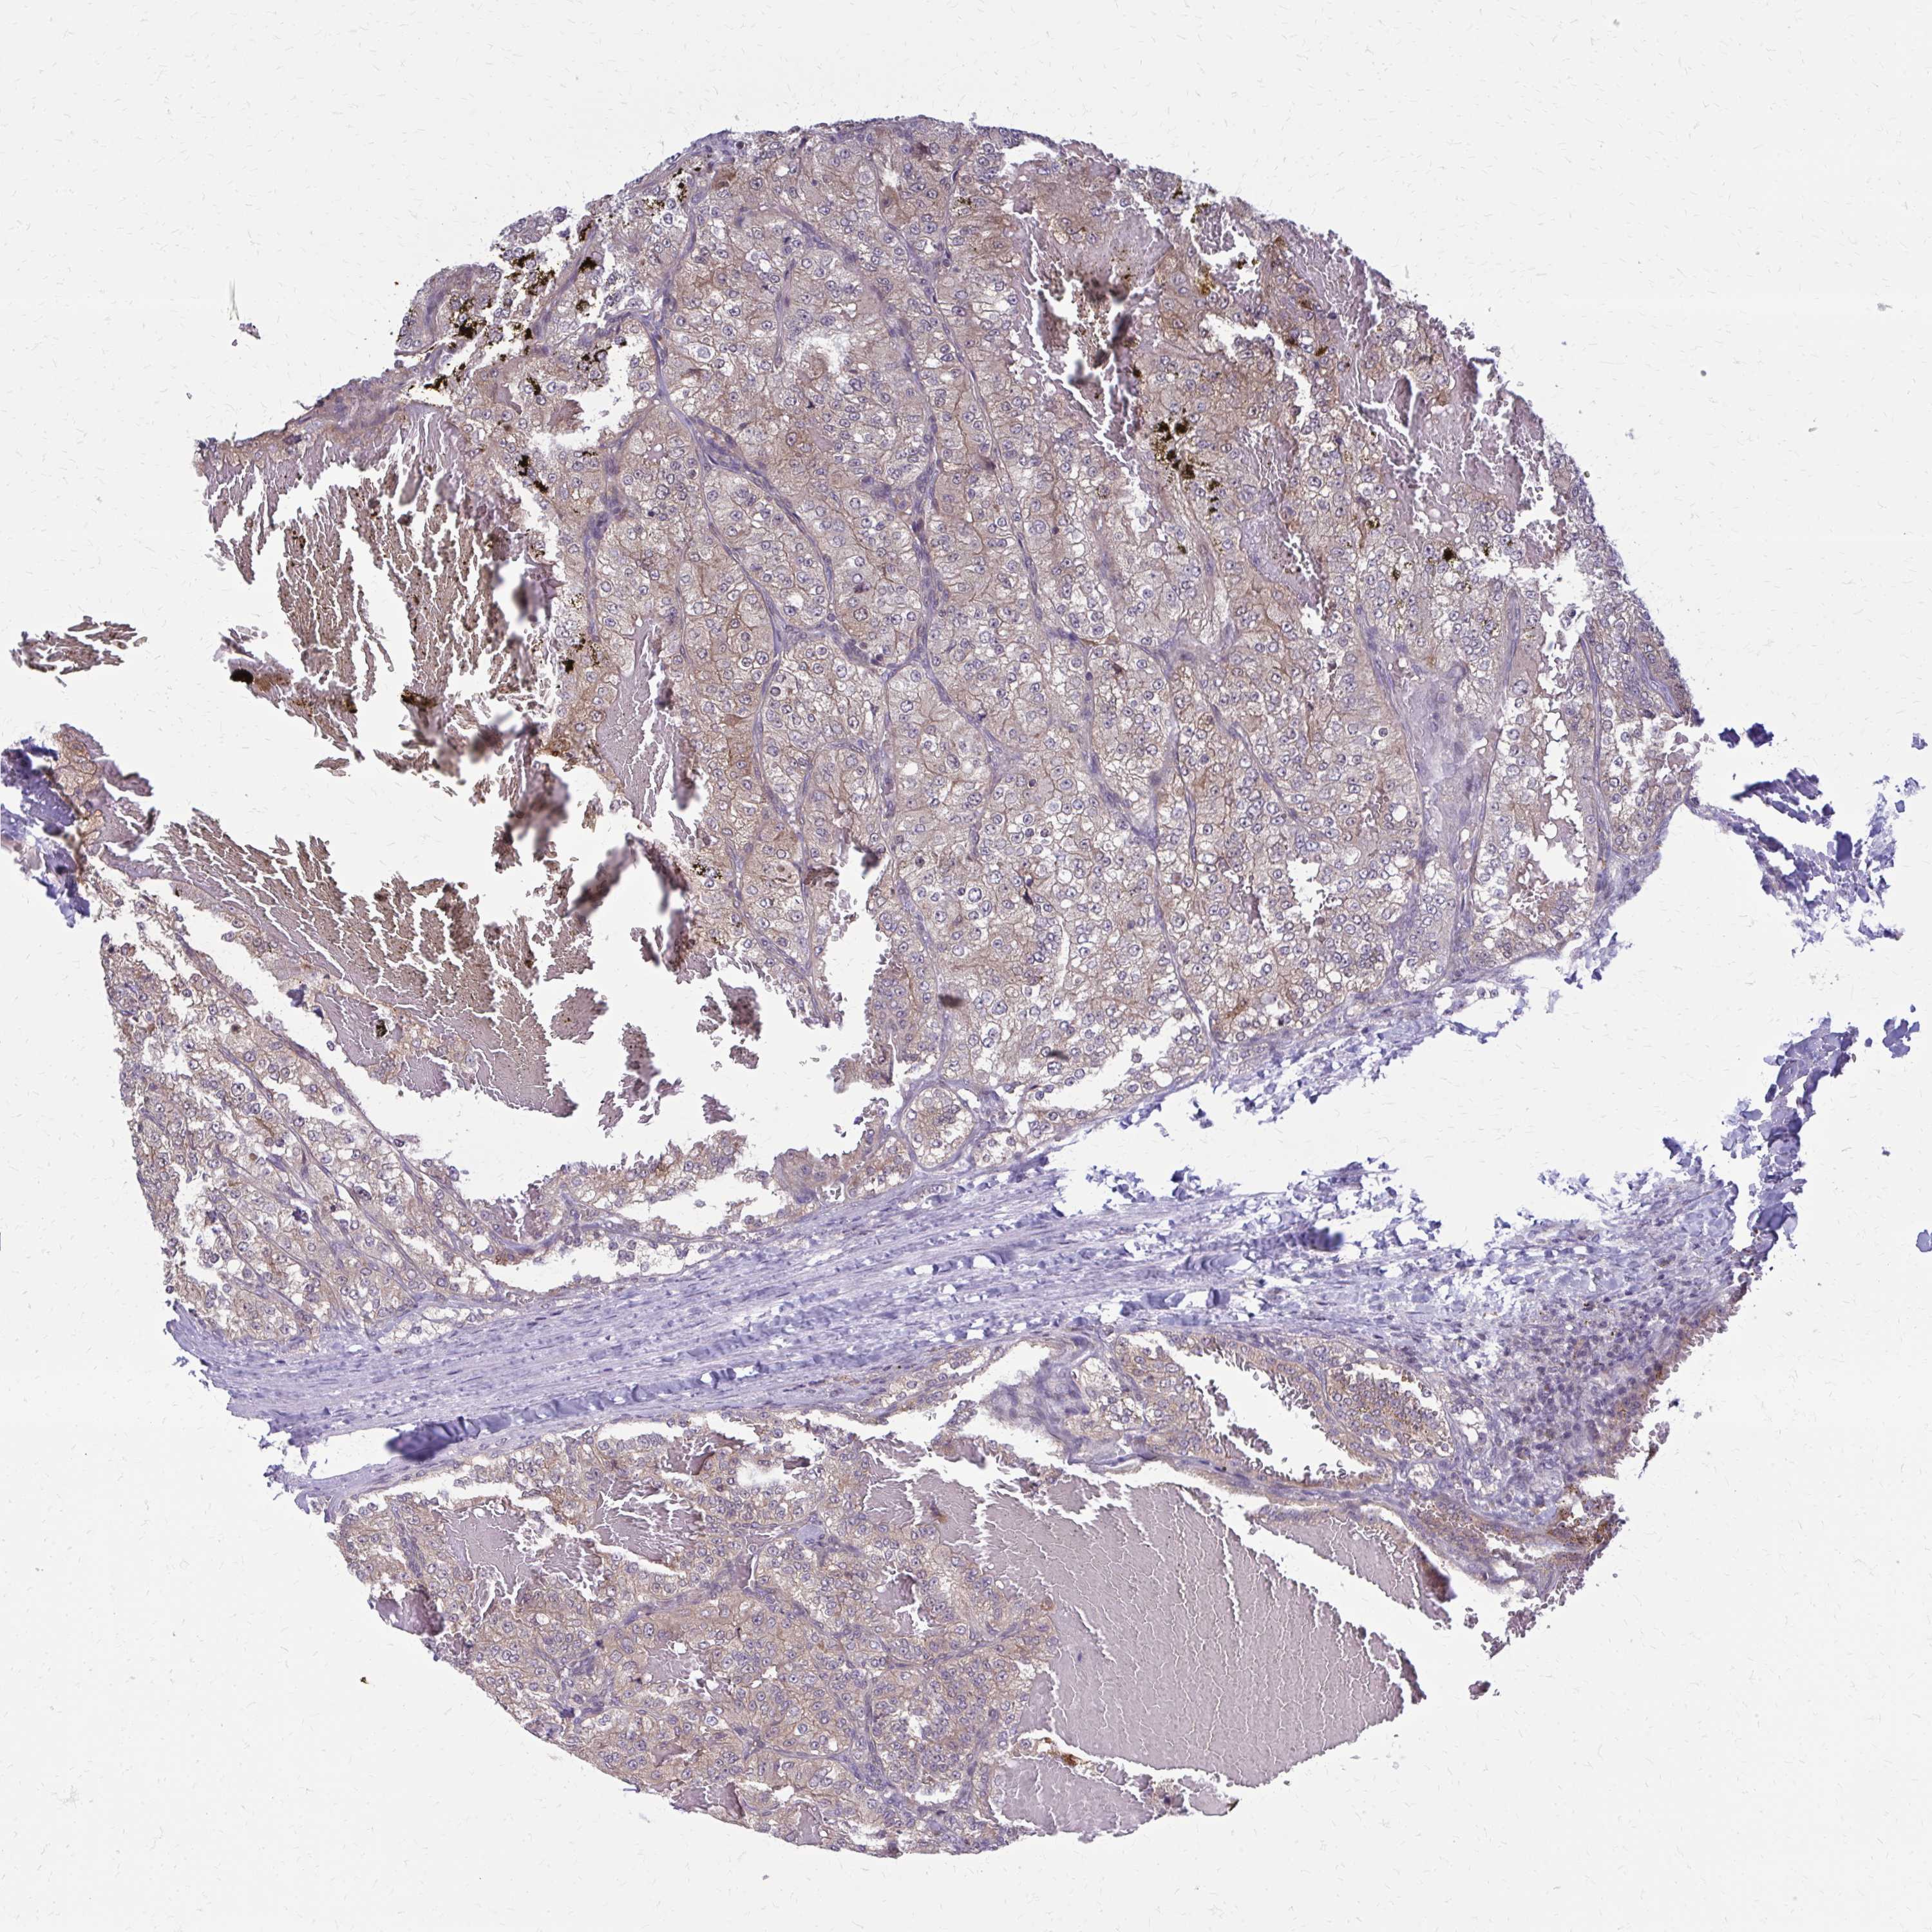

KIDNEY RENAL CLEAR CELL CARCINOMA (TCGA) - Interactive survival scatter ploti

The Survival Scatter plot shows the clinical status (i.e. dead or alive) for all individuals in the patient cohort, based on the same data that underlies the corresponding Kaplan-Meier plots. Patients that are alive at last time for follow-up are shown in blue and patients who have died during the study are shown in red.

The x-axis shows the expression levels (FPKM) of the investigated gene in the tumor tissue at the time of diagnosis. The y-axis shows the follow-up time after diagnosis (years). Both axes are complimented with kernel density curves demonstrating the data density over the axes. The top density plot shows the expression levels (FPKM) distribution among dead (red) and alive patients (blue). The right density plot shows the data density of the survived years of dead patients with high and low expression levels respectively, stratified using the cutoff indicated by the vertical dashed line through the Survival Scatter plot. This cutoff is automatically defined based on the FPKM cutoff that minimizes the p-score. The cutoff can be changed by dragging the vertical line or by entering a cutoff value in the square labeled "Current cut-off".

Under the Survival Scatter plot the p-score landscape (black curve; left axis) is shown together with dead median separation (red curve; right axis). Dead median separation is the difference in median mRNA expression between patients who have died with high and low expression, respectively. It is calculated as follows: median FPKM expression of dead patients with high expression - median FPKM expression of dead patients with low expression. This is intended to aid the user in visually exploring custom cutoffs and the associated p-scores and dead median separation.

Individual patient data is displayed and can be filtered by clicking on one or more of the category buttons on the top of the page. Categories describing expression level and patient information include: high, low, alive, dead, female, male and tumor stages. The scale of the x-axis can be toggled between linear and log-scale by clicking on the "x log" button. Mouse-over function shows TCGA ID, patient information and mRNA expression (FPKM) for each patient.

& Survival analysisi

Kaplan-Meier plots summarize results from analysis of correlation between mRNA expression level and patient survival. Patients were divided based on level of expression into one of the two groups "low" (under cut off) or "high" (over cut off). X-axis shows time for survival (years) and y-axis shows the probability of survival, where 1.0 corresponds to 100 percent.

DBI is potential prognostic, high expression is unfavorable in Kidney Renal Clear Cell Carcinoma (TCGA)

Best expression cut offi

Based on the FPKM value of each gene, patients were classified into two groups and association between prognosis (survival) and gene expression (FPKM) was examined. The best expression cut-off refers the FPKM value that yields maximal difference with regard to survival between the two groups at the lowest log-rank P-value. Best expression cut-off was selected based on survival analysis .

When clicking on this number, the vertical dashed line indicating cut-off, the interactive survival plot, and the Kaplan-Meier curve will be adjusted to show results based on the best expression cut-off.

: 308.47

TCGA RNA samplesi

RNA-seq data is reported as average FPKM (number Fragments Per Kilobase of exon per Million reads), generated by the The Cancer Genome Atlas (TCGA) .

Normal distribution across the dataset is visualized with box plots, shown as median and 25th and 75th percentiles. Points are displayed as outliers if they are above or below 1.5 times the interquartile range. FPKM values of the individual samples are presented next to the box plot.

Average pTPM 266.1

Number of samples 521